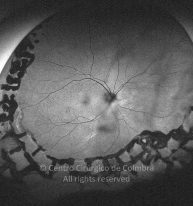

Paciente de 37 años con traumatismo contundente y ruptura del globo ocular. Presenta ruptura esclero-uveal, hifema, hemovítreo, desgarro periférico y temporal de la retina, hemorragias subretinianas y múltiples desprendimientos serosos.

MAVC: 20/25 OD, nueve años después de las cirugías (sutura escleral de la desinserción del músculo recto externo, vitrectomía posterior y fotocoagulación láser en el borde del desgarro retiniano, desprendimiento de retina inferior con proliferación vitreorretiniana y líquido subretiniano con algo de sangre; peeling de la membrana epirretiniana y maculorrexis de la MLI).